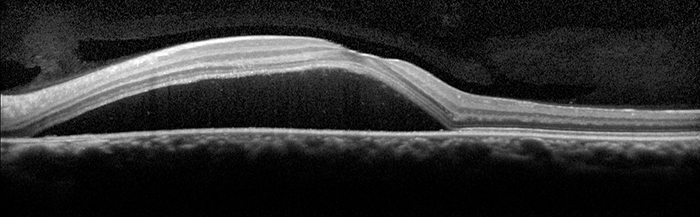

Optical coherence tomography (OCT)

An OCT scan is a quick, painless and non-invasive imaging technique. The scan uses light to produce very high-resolution cross-sectional images of the tissue layers of the retina.